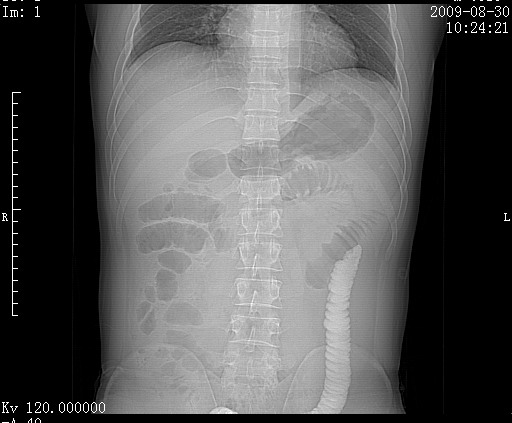

胃镜:急性胃炎。立位腹平片:未见异常。

下面是ct平扫,降结肠内是对比剂。

术前影像诊断:上段空肠急性缺血性坏死并腹水。建议手术治疗。

术中见上段空肠约70cm长范围坏死,从屈氏韧带远端约10cm处开始。坏死肠管肿胀变形变色,管壁明显环形增厚,部分聚成大肿块,无扭转和套叠。肠系膜上动脉分支内广泛泥沙状血栓。肠切除。

临床诊断:肠系膜上动脉梗塞并急性肠坏死。

本例没有增强,所以要肯定为肠系膜上动脉梗塞是不可能的。我认为只要肯定是肠坏死并建议立即手术也就没错。临床医生认为如果增强的话,仅仅是你们多了一例教学片。